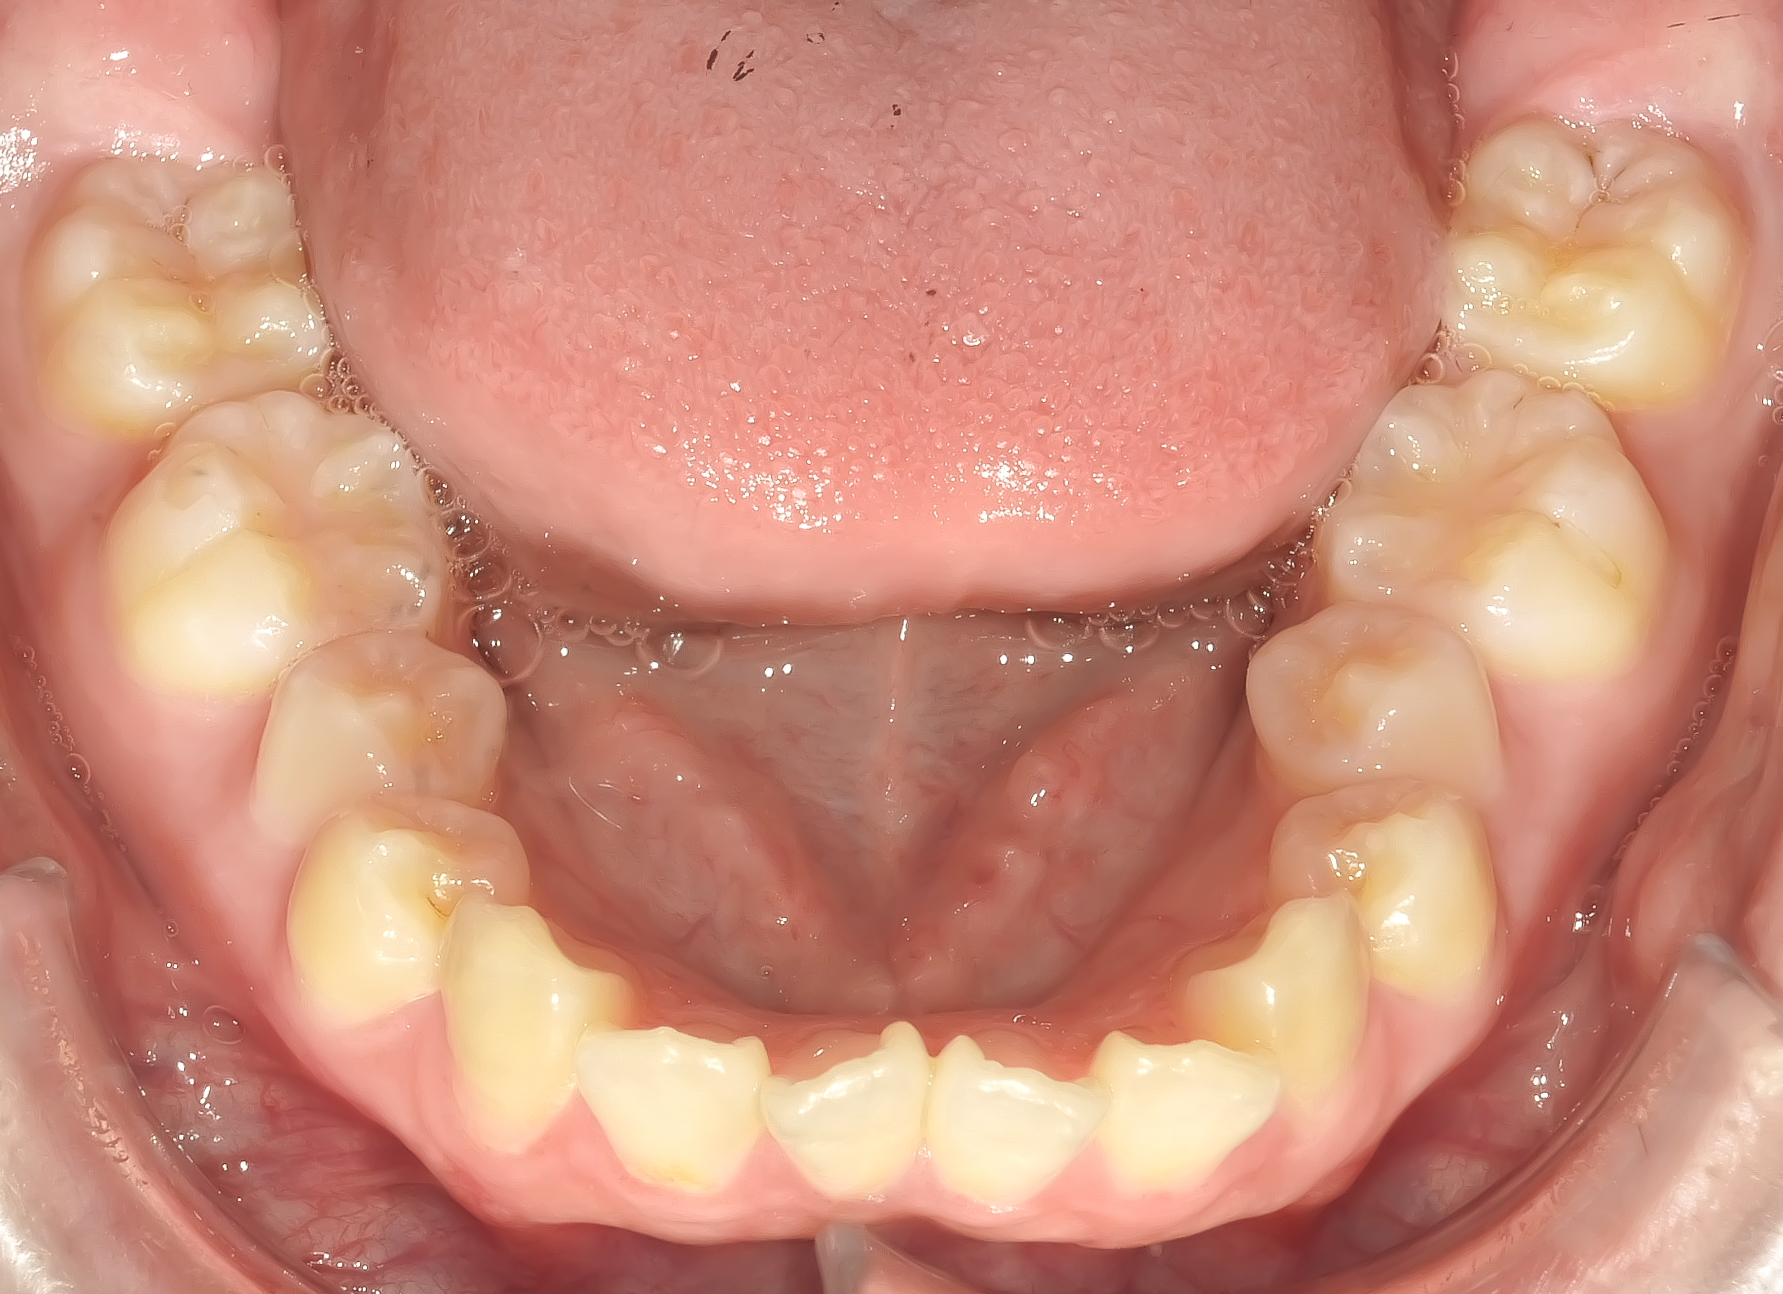

下顎の前歯に叢生(ガタガタ)を認めます。

治療終了時の写真です。

上下の歯の真ん中が揃い、きれいに並んでいます。

ほぼすべての歯が歯列弓上にきれいに並んでいます。

上下ともしっかり並びました。